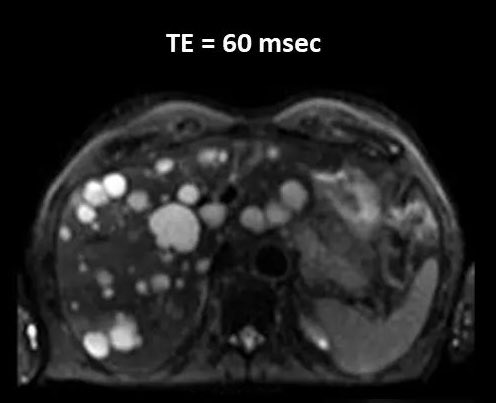

To quantitatively compare the diagnostic values of conventional diffusion-weighted imaging (DWI) and introvoxel incoherent motion (IVIM) analysis of microstructural differences for clear cell renal cell carcinoma (ccRCC). lnkd.in/eyHzyFrg